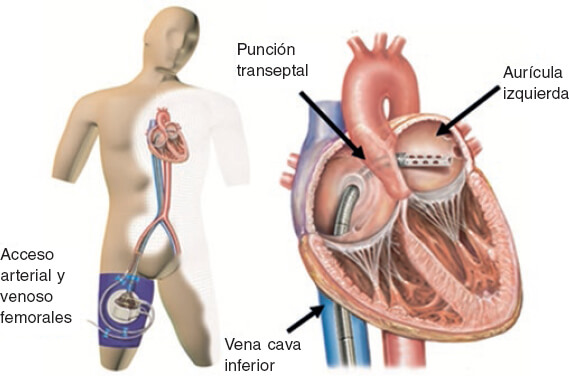

El TandemHeart (figura 1) es un dispositivo de asistencia circulatoria temporal, externo y capaz de proporcionar un flujo continuo de 4 l/min43. Contiene 3 subsistemas y es el único dispositivo diseñado para atravesar el septo interauricular, mediante una cánula de 21 Fr que queda alojada en la aurícula izquierda. La sangre oxigenada se succiona desde la aurícula izquierda y se retorna a través de una bomba centrífuga que proporciona un flujo continuo a través de una cánula de 12 Fr en la arteria femoral o de 15-17 Fr en la arteria ilíaca.

Figura 1. Esquema de funcionamiento del dispositivo TandemHeart con acceso periférico femoral. Drenaje de la sangre oxigenada por medio de una punción transeptal de la aurícula izquierda que retorna a través de la arteria femoral.